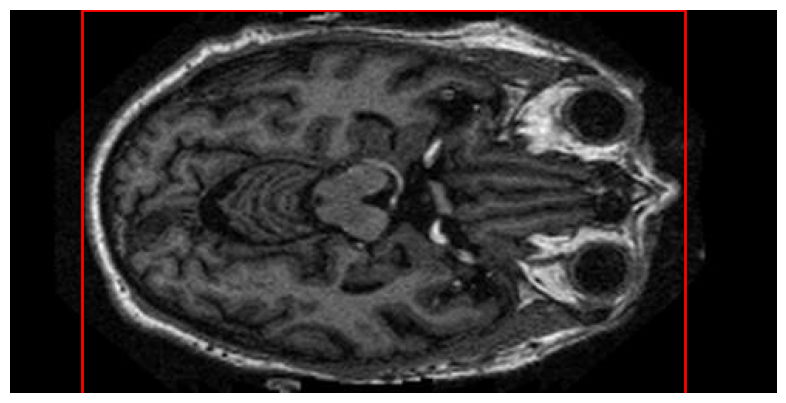

Next step is to calculate the bounding box for each slice of the same patient. The focus here is to select the largest bounding box from these slices as the ROI for that particular patient. In this way we ensure that our ROI will be shorter from the whole image and will include all the MRIs essential information. After applying Otsu’s method for thresholding the MRI images, we label the pixels and we calculate the bounding box, which is the smallest rectangle that can enclose the labeled region. The margins of this bounding box are determined by the extremities of the region. Fig. 2 shows an indicative ROI calculated out of the slices of a patient.

Thus, we calculate the sum of Canny edges within the ROI of each slice. This sum serves as a numerical representation of edge density or detail level in each slice. The distribution of these values across continues slices of the same patient follows a pattern akin to a Gaussian distribution, Fig. 3.

The lower slices, typically showing minimal brain tissue, exhibit fewer edges. As the slices progress to the middle of the brain, where structures like the nose, eyes, and brain tissues are more pronounced, the edge sum reaches its peak, indicating the highest complexity and detail level. Beyond this region, towards the top of the head, the complexity decreases again, mirrored by a reduction in the sum of edges.

Based on the analysis incorporating Otsu’s method and Canny Edge Detection, 140 continuous slices with maximal information were selected, as shown in Fig. 1. These slices, identified for their significant Canny Edge sums, ensure the inclusion of the most informative brain regions. Algorithm 1 summarizes these steps, outlining the process for the effective selection of these key slices.